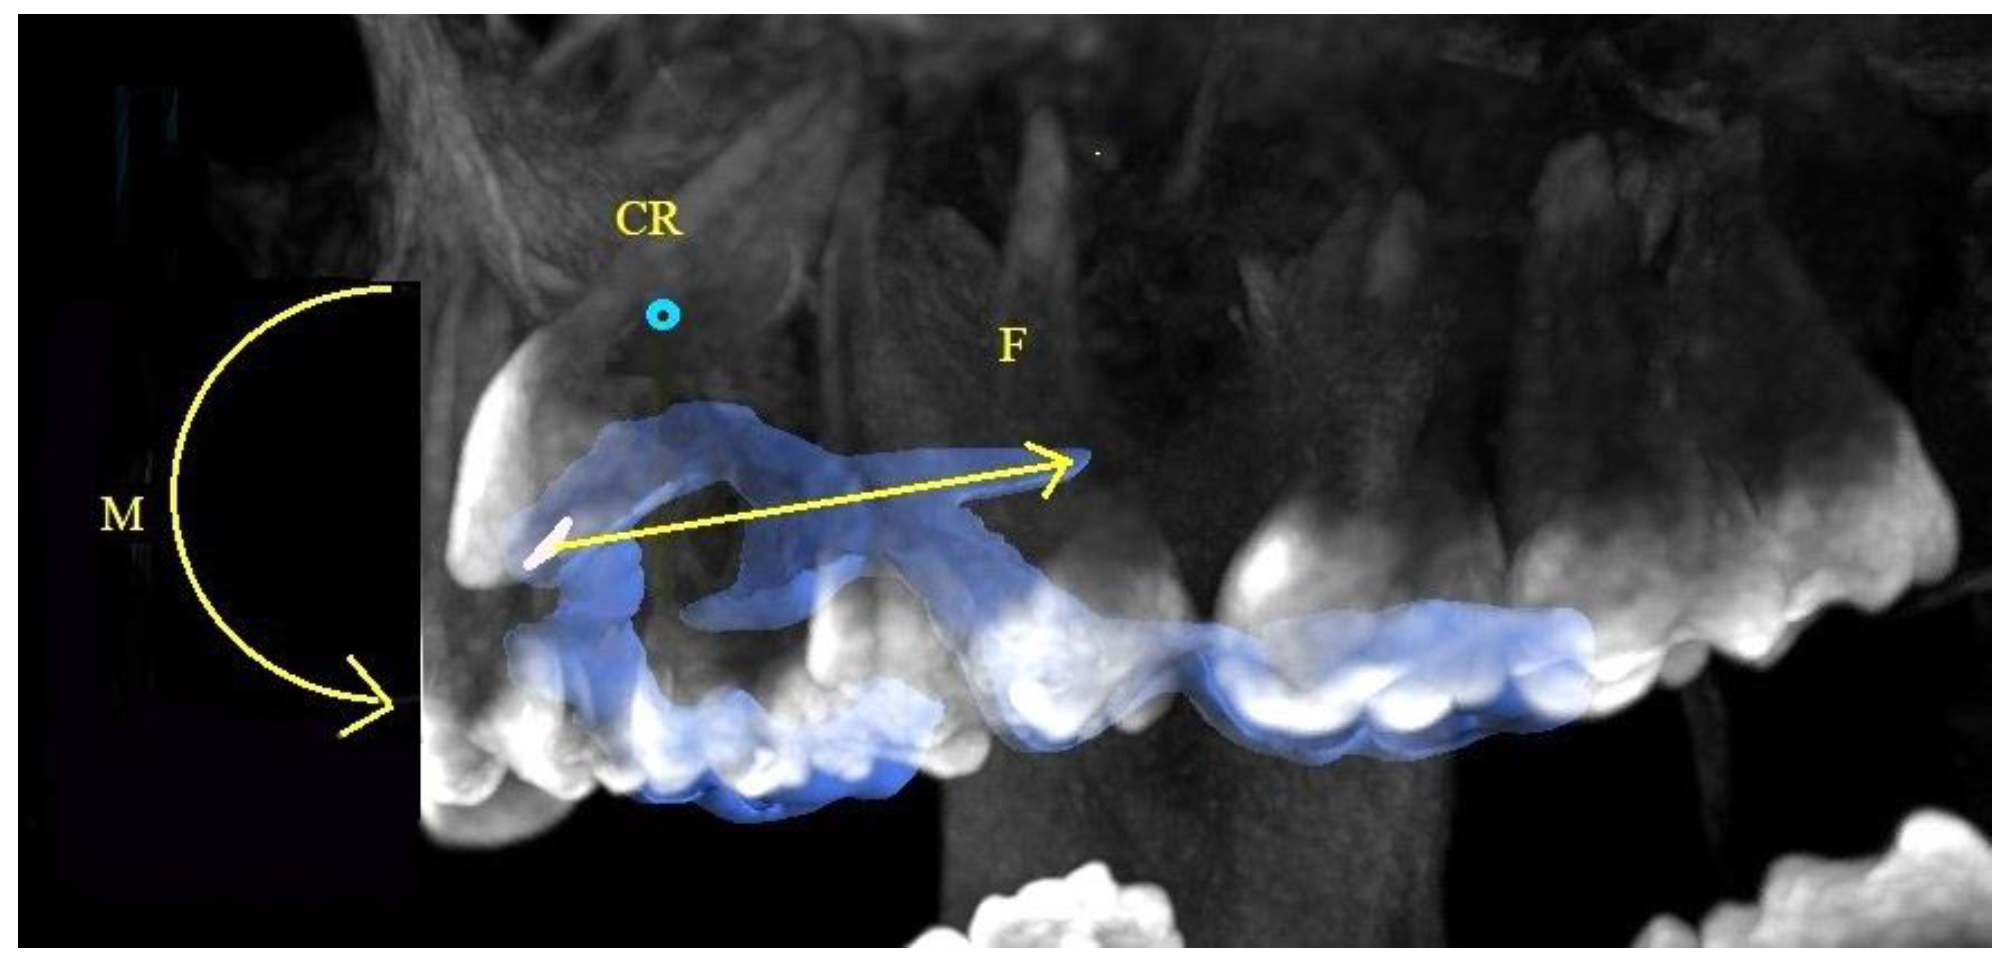

2. Materials and Methods

3. Results